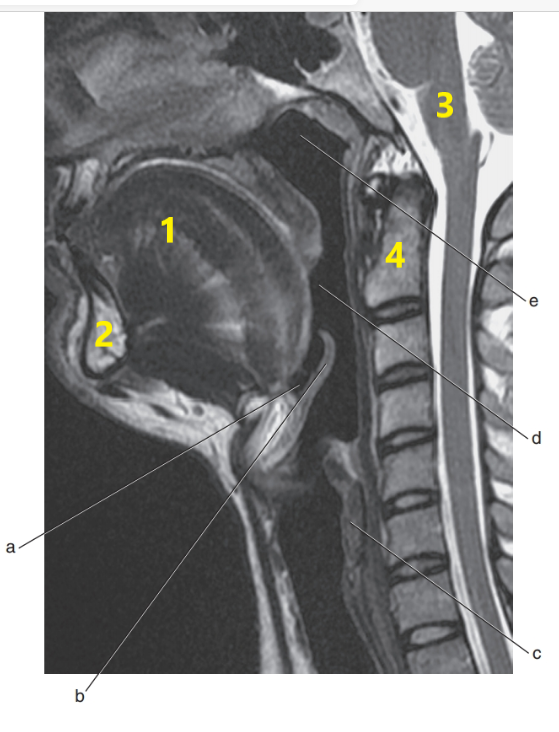

What is # 1 ?

Mandible

What is # 4 ?

C-1/C-2

Tongue

What is # 3 ?

Brain stem